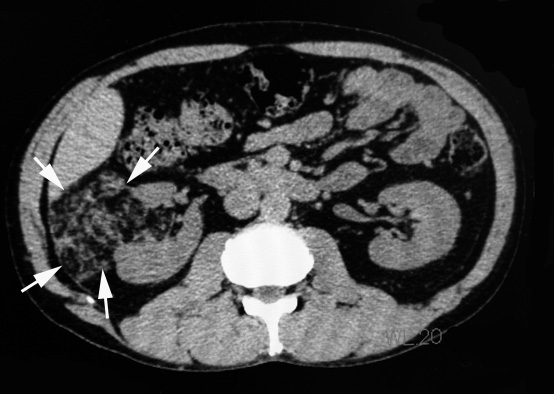

右腰痛のため受診。精査で右腎に出血をともなう直径7cmの腫瘤を認めた。angiomyolipomaの出血と診断し, 出血の消失をまって右腎摘出術をおこなう。

- 典型的angiomyolipoma(AMLoma)は腎実質の一部を置換する腎内腫瘍である。病変サイズは大小さまざまで被膜病変は数ミリを越すことはまれな一方, 腎実質腫瘍は最大径が3-20cm(平均9.4cm)となり大型の腫瘤は周囲の構造を圧迫することになる。通常は単発であるが20%の例では多発する。

- 通常分葉状で黄色, わずかに油脂状の腫瘤。平滑筋が主要成分の場合は灰白色で硬い。出血はよく起こり症状のある例ではとくにありふれた現象である。腫瘍全域におよぶ出血もありうる。